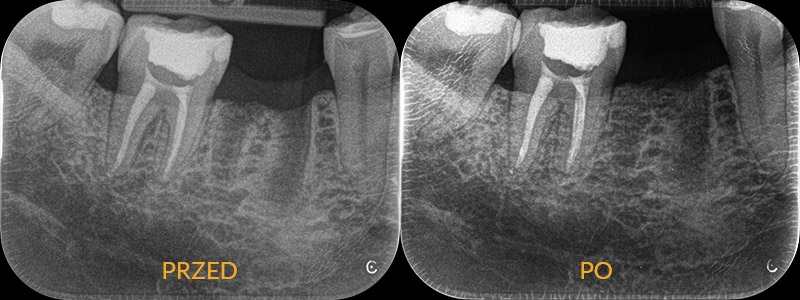

Reendo i odbudowa protetyczna

Pacjent zgłasza się ze złamaną ścianą zęba. Chce jak najszybciej odbudować nadłamaną część. 15 lat temu ząb był leczony kanałowo. Kontrolne zdjęcie wykazuje nieprawidłowo wypełnione kanały korzenia, wypełnienie jest nieszczelne, pojawiła się też rozległa próchnica. Lekarz nie może podjąć się odbudowy zęba, bez wcześniejszego powtórnego leczenia kanałowego. Usuwa stary materiał, opracowuje kanały na nowo, wypełniając je na koniec ciepłą gutaperką. W związku z rozległym uszkodzeniem korony zęba zostaje zaplanowana odbudowa protetyczna.